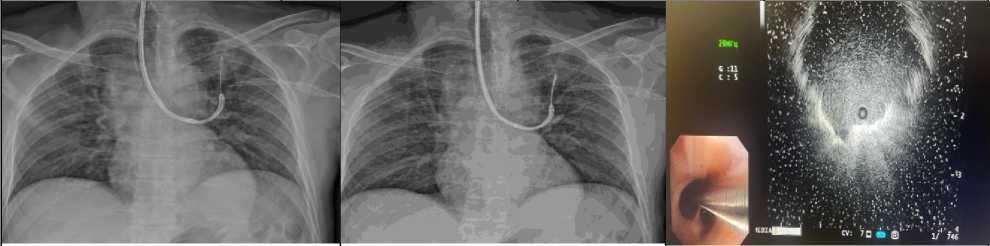

Клинический пример

Пациент А., 57 лет. По месту жительства пациенту была проведена компьютерная томография (КТ) органов грудной клетки, которая выявила очаг в сегменте 2 левого легкого. В целях дальнейшего обследования пациент обратился в Российский научный центр рентгенорадиологии (РНЦРР).

При пересмотре данных КТ в периферической зоне сегмента 2 правого легкого был обнаружен солидный очаг с четкими и ровными контурами, который располагался рядом с ветвью Б2. Был сделан вывод о возможном злокачественном характере этого образования.

Для подтверждения изменений в легком была проведена бронхоскопия с бронхобипсией очага под рЭБУС и рентгенконтролем с предварительной КТ навигацией. На основе данных КТ-навигации была определена траектория до зоны интереса. На сканограмме, полученной с помощью радиоэлектронной навигации, на 10-13 часах условного циферблата относительно зоны интереса была видна тень очага. По данным рентгеноскопии биопсийные инструменты находились в зоне интереса, что позволило выполнить биопсию.

Цитологическое исследование биопсийного материала подтвердило наличие клеток аденокарциномы (Рис. 7).

б.

а.

в.

г.

д.                                          е.                                         ё.

ж.                                                      з.

Рис. 7. (а, б) КТ. Легочный режим. (а) Криволинейная реконструкция; (б) Фронтальная плоскость. В периферических отделах С2 левого легкого солидный очаг, с четкими и неровными контурами, с «подходящей» ветвью Б2. (в) Рентген легких. Прямая проекция. В верхней доле левого легкого округлой формы затенение. (г) Бронхоскопия под контролем рЭБУС. рУЗ-датчик в толще затенения в верхней доле левого легкого. (д) Бронхоскопия с щеточной бронхобиопсией под рентген контролем. (е) Бронхоскопия с щипцовой бронхобиопсией под рентген контролем. (ё) УЗ сканограмма. УЗ-минизонд в подходящем к очагу бронхе. (ж) Аденокарцинома легкого. Цитологическое исследование. Окраска азуром и эозином. Объектив 20х. В крови присутствуют различные клетки: бронхиального эпителия, макрофаги и комплексы клеток аденокарциномы. (з) Макропрепарат в разрезе. Фрагмент ткани легкого размерами 10,5 х 3,5 х 4 см. В ткани легкого субплеврально определяется опухолевый узел №1 размерами 2,9 х 3,0 х 2,7 см. Ткань опухоли плотная серая. Опухоль врастает в висцеральную плевру легкого. В этом месте - ее втяжение на участке 1 х 0,5 см.